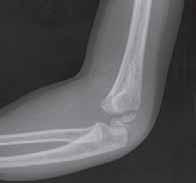

Rozpoznanie

Objawy złamania to silny ból uniemożliwiający stanie i chodzenie, zniekształcenie obrysów stawu kolanowego przez krwiak i różnego stopnia przemieszczenie nasady kości piszczelowej. Należy dokładnie zbadać stan ukrwienia i unaczynienia kończyny pod kątem objawów uszkodzenia tętnicy podkolanowej i nerwu strzałkowego. Trzeba ocenić bolesność uciskową oraz napięcie w przedziałach powięziowych podudzia: przednim, bocznym, tylnym powierzchownym i tylnym głębokim. U pacjentów z podejrzeniem wzmożonego ciśnienia wewnątrzprzedziałowego należy wielokrotnie powtarzać badanie ukrwienia i unerwienia kończyny, a w razie zaistnienia wskazań wykonać bezpośredni pomiar ciśnienia w przedziałach. Powinno się zawsze podejrzewać możliwość uszkodzeń więzadłowych współistniejących ze złamaniem. Badania obrazowe to RTG w pozycji AP, bocznej i skośnej. Wykonanie badania TK może być konieczne w celu pełnej oceny rozległości

złamania. W przypadku podejrzenia uszkodzenia tętnicy podkolanowej należy wykonać angio-TK lub arteriografię.

Leczenie

Leczenie złamania bliższej nasady piszczeli w przypadku uszkodzenia typu 1 i 2 według Saltera i Harrisa leczymy nieoperacyjnie. Należy wykonać zamkniętą repozycję i unieruchomić w opatrunku gipsowym udowym w zgięciu kolana 30–60°, zapewniającym najlepszą stabilność odłamów. Okres unieruchomienia wynosi od 6 do 7 tygodni. Po tym czasie usuwamy gips i zaczynamy ćwiczenia zwiększające zakres ruchomości stawu kolanowego oraz wzmacniające siłę mięśnia czworogłowego. Ważne jest, by prowadzić częste kontrole stanu ukrwienia i unaczynienia oraz kontrole radiologiczne w celu wykrycia ewentualnych przemieszczeń odłamów. Złamania pierwotnie niestabilne lub wtórnie przemieszczone wymagają zamkniętej repozycji stabilizacji drutami K. Typ 3 i 4

Złamania rzepki i podudzia

złamania według Saltera i Harrisa wymaga leczenia operacyjnego w postaci otwartej repozycji i stabilizacji śrubami. Należy unikać krzyżowania metalu zespalającego z chrząstką wzrostową. Kończynę zgiętą w kolanie do 30° unieruchamia się w gipsie udowym na okres 6–8 tygodni. Po tym czasie rozpoczynamy ćwiczenia czynne poprawiające zakres ruchomości kończyny.